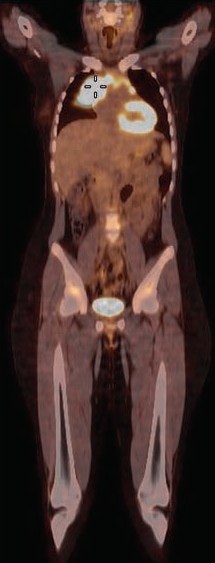

FDG-PET/CT can play a valuable role in directing image-guided biopsies of pediatric cancer patients, given its ability to detect and discern between malignant and benign regions, according to a study by a group from Saudi Arabia and Canada published in the March issue of the American Journal of Roentgenology.

Among some four dozen pediatric patients with known or suspected malignancies, the researchers found 36 cases in which FDG-PET images were concordant with biopsy results, and only one case of disagreement. The findings suggest FDG-PET/CT would be useful in identifying the best site for biopsy in young patients, the group concluded (AJR, March 2017, Vol. 208:3, pp. 656-662).

Forty-five subjects were imaged on a 16-slice PET/CT scanner (Gemini GXL, Philips Healthcare) in the supine position with normal respiration. Whole-body imaging began 60 minutes after injection of 5.2 MBq/kg of body weight of FDG, up to a maximum of 370 MBq (10 mCi).